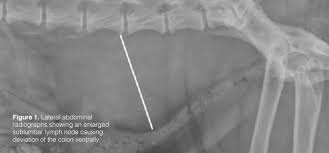

Department Of Surgery Liver Metastases from surgery.ucsf.edu The second kind of lung cancer in dogs is called metastatic lung cancer, which means the cancer originated somewhere else in the body, but has spread to the lung. The best way to increase a dog's prognosis against metastatic cancer is to be aware of the signs and to detect it early enough that treatment can be successful. Many owners choose to euthanize their pet to ease their suffering. Lung metastasis in dogs (and sometime it happens to cats, too) is a tough situation to experience. When the tumors have grown in size and made their way into the lymph nodes of your dog's lymphatic system, the prognosis is far lower, with the average survival time coming in at about two months. In this article we will help you understand the diagnosis of cancer in dogs. They can be detected on chest radiographs or computed tomography (ct) scanning. If, on the other hand, the dog has multiple tumors, or if the cancer has spread to the lymph nodes, the life expectancy is only about 2 months.

As best as you can, be attentive to your dog's breathing patterns, and protect it from exposure to second hand smoke. For small, solitary tumors that have not metastasized (spread), the average survival time with surgery alone is 20 months. If a dog is experiencing any serious respiratory symptoms or decline in their health, this is often a sign that the cancer is severe or it has spread to other parts of the body. In general, the prognosis for treating cases of metastatic cancer in dogs depends on how early the metastatic tumor is identified and how invasive it is. Following are some symptoms of end stage lung cancer in dogs and some tips for those who chose to provide their dog with some hospice care. End stage lung cancer in dogs will cause the. In this group, more than 50% are expected to live 1 year after the surgical removal of the mass. Pulmonary adenocarcinoma is cancer of the lungs, which can be primary (originates in the lungs) or secondary (originates somewhere else in the body), is a serious disease that can be fatal if not found and treated early. The lung is the most common location for metastatic osteosarcoma. Recovery of metastic neoplasia (cancer) in dogs unfortunately, the prognosis for metastatic neoplasia is grave due to the fact that the cancer has already spread. In this group, more than 50% are expected to live 1 year after the surgical removal of the mass. If, on the other hand, the dog has multiple tumors, or if the cancer has spread to the lymph nodes, the life expectancy is only about 2 months. Primary lung cancer, which is quite rare and metastatic lung cancer, spread from other areas of the body.